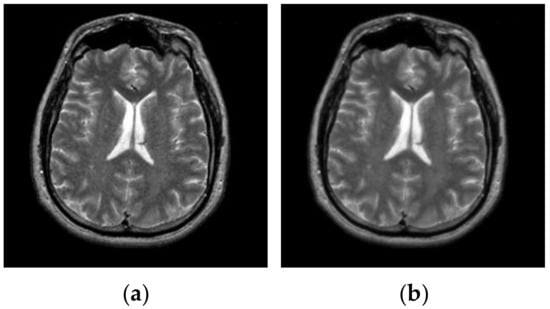

After hybrid L1 − L0 layer decomposition, the base layer of original image is used for segmentation in the framework of the proposed algorithm. Figure 7 displays an example of decomposition. In Figure 7, the first column contains two original images, and the second column contains two corresponding base layers. From Figure 7b, it can be seen that the base layers are visually smooth, and eliminate some weak edges.

Figure 7.

Original images and their corresponding base layers. (a) Original images, (b) base layers.